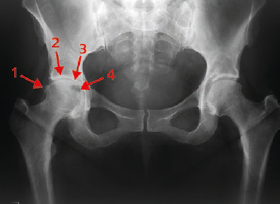

Bildgebende Diagnostik: Die Röntgenuntersuchung unter Belastung gilt als Goldstandard für die Diagnose der Hüftgelenksarthrose. Sie zeigt charakteristische Veränderungen wie:

- Gelenkspaltverengung

- Osteophytenbildung (Knochensporne)

- Subchondrale Sklerosierung

- Zystenbildung im Knochen